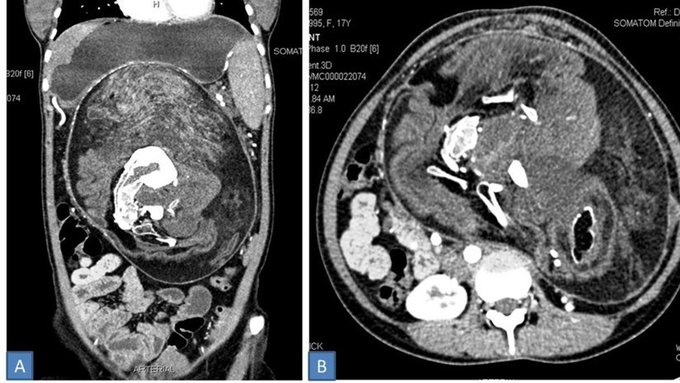

Los médicos han extraído del abdomen de una joven de 17 años, un 'hermano gemelo' que se encontraba en el interior de su cuerpo durante toda su vida sin que ella lo supiera.

Se trata del fenómeno llamado 'fetus in fetu' (FIF), que se produce debido a una "rara anomalía del desarrollo en la que un feto malformado se halla dentro del cuerpo de otro gemelo".

Ante la preocupante situación, la joven acudió con el doctor y se reveló que tenia pegado en su abdomen el feto de su “hermano gemelo” que medía 30×16×10 centímetros e incluso tenía pelos y "múltiples dientes".

El feto de su “hermano gemelo” había desarrollado un tumor desde que la joven tenia 12 años, razón de los dolores y molestias que presentaba día a día.

Tras una intervención quirúrgica, los doctores lograron extirpar al “hermano gemelo” de la joven de 17 años de edad, la cual afirma que su abdomen ya es plano y se “siente muy bien”.